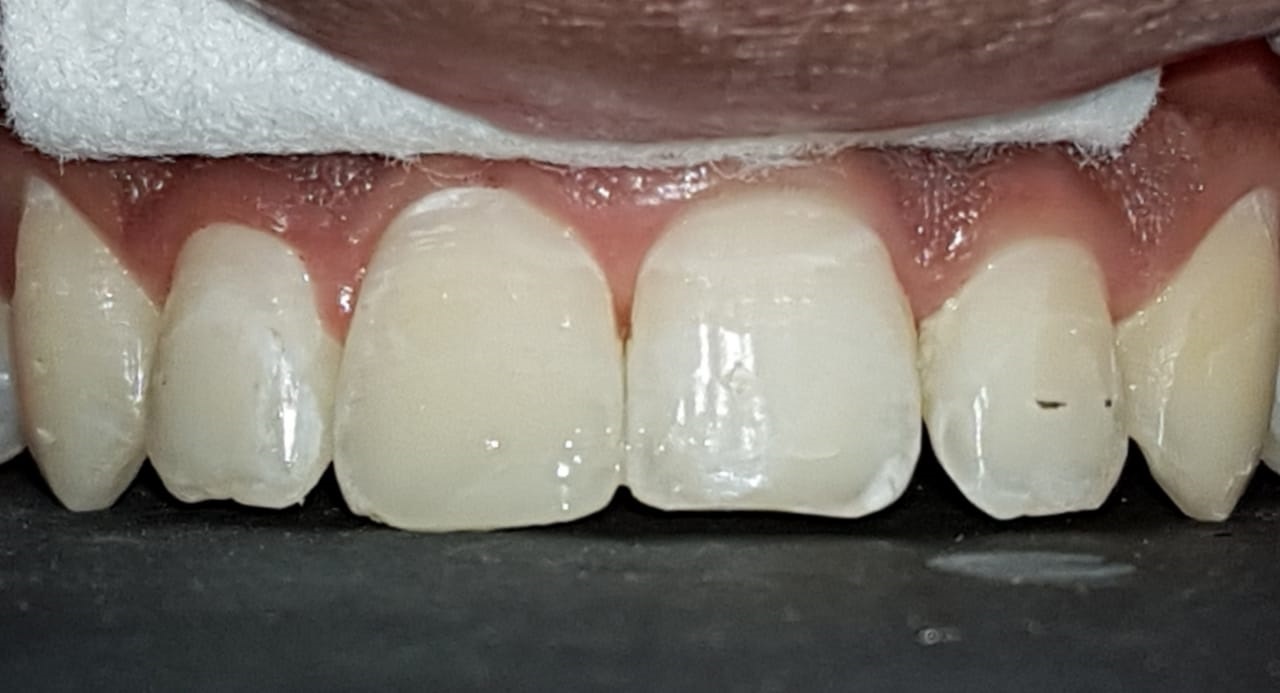

समोरचे दात जर किडलेले असतील तर त्यामध्ये दातांच्या रंगाचे फिलिंग (कंपोझिट) करता येते. खूपच किडलेल्या दातांना रूट कॅनाल ट्रीटमेंट करून, अगदी हुबेहूब नैसर्गिक दिसणारे सिरामिक किंवा झिरर्कॉनियम चे दातही बसविता येतात .

We do Composite( tooth colored )fillings, Laminates, veneers, Thineers, Laminates etc.

Prosthodontics refers to the replacement of missing teeth. Crowns and bridges are placed. made up of metail or ceramic,designed to look exactly like natural teeth. Option such as zirconia, E-mac and Lava (5 to 15 years gurantee) are available as well as implants-the most contemporary way to replace single, multiple or all teeth.

From subtle changes to major repairs, we can perform a variety of procedures to improve your smile. There are many techniques and options to treat teeth that are discolored, chipped, misshapen or missing the dentist can reshape your teeth, close spaces, restore worn or short teeth or alter the length of your teeth. Common procedures include bleaching, bonding, caps, crowns, veneers, and reshaping and contouring.